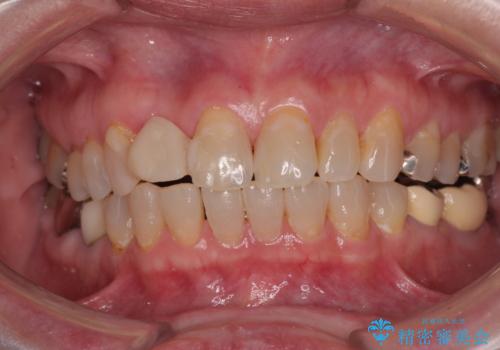

- 前歯のインプラント治療を検討して様々医院を探していたところ、1回の手術で治療ができるとのことで来院された患者様です。

長期間の治療と外科処置の回数が多くなることを懸念して、なかなかインプラント治療に乗り出せなかったそうですが、1DAYインプラントというものがあることを知り、当院にいらっしゃいました。

仮歯を事前に用意し、インプラント埋入時に即日で仮歯を装着する、即時荷重インプラントの計画で治療を進めて行くこととしました。